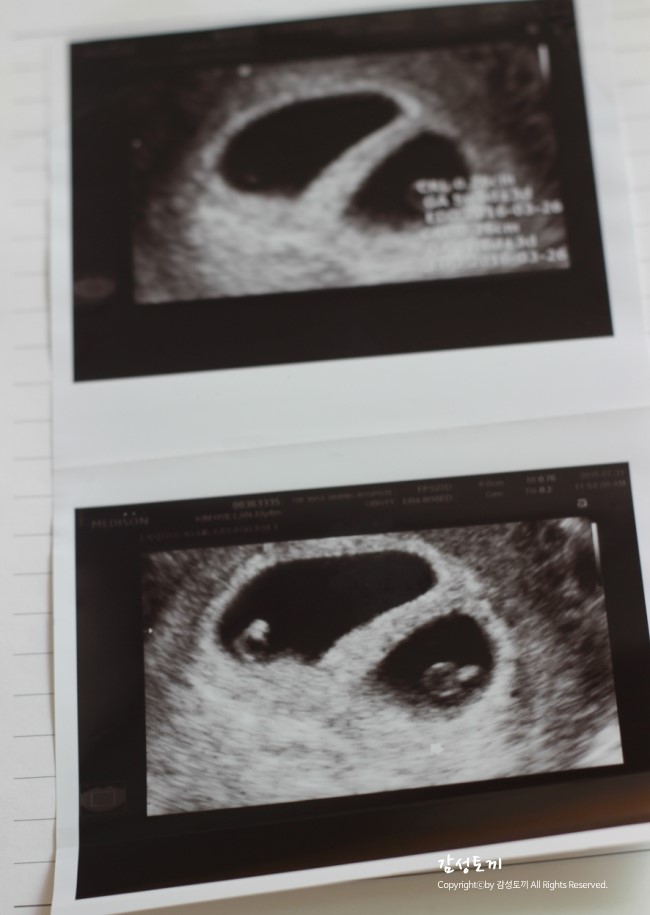

쌍둥이 임신 - 행복, 여름이와의 만남

행복, 여름이와의 만남 첫째유니가 아직 어려서 둘째를...